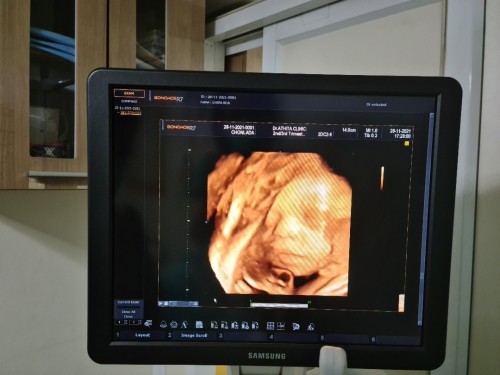

ทีมลูกชาย 8กุมภาค่ะแม่ๆ ท้องแรกตื่นเต้นมากๆค่ะ